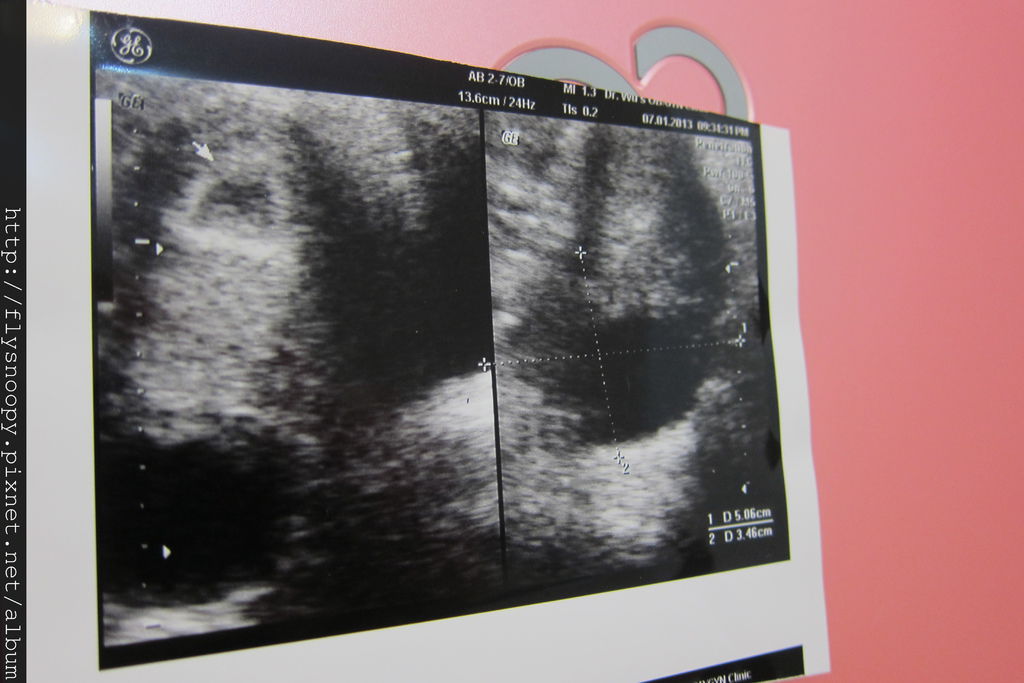

2013.1.7照到胚囊囉

2013.1.16也是因為有分泌物所以去看診,發現超音波照得越來越清楚囉~~~